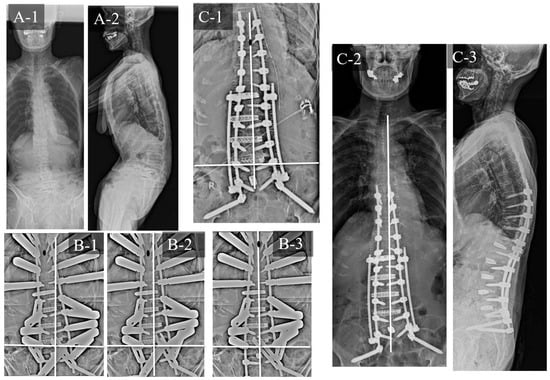

3.3. Case Study 3: RR and KR